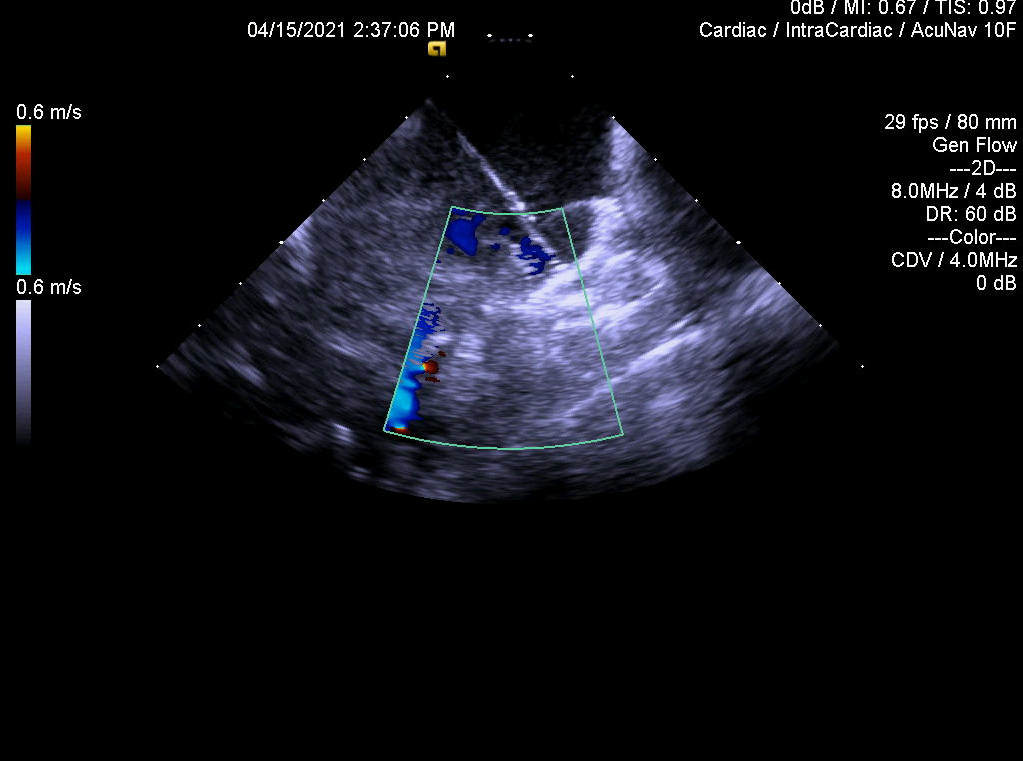

亮点2:ICE指导术中评估左心耳封堵情况

亮点3:ICE多维度评价左心耳封堵结果—锚定,有无露肩,压缩比测量,有无残余分流